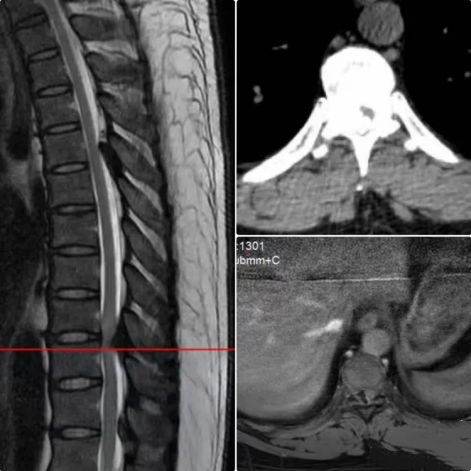

术前影像资料

术后复查影像资料